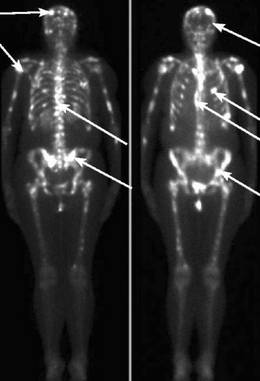

Метастазы в костях – сколько осталось жить?

Вторичный раковый процесс в костной ткани достаточно быстро диагностируется, что дает возможность своевременно начать лечение. Наиболее частой причиной такого поражения выступают злокачественные новообразования простаты и органов женской половой системы. Раковые клетки проникают в костную ткань с током крови или лимфы.

Симптомы онкологического поражения костей проявляются постепенным нарастанием болевого синдрома, образованием припухлости мягких ткани, частыми патологическими переломами и явлениями системной интоксикации.

Терапия злокачественных новообразований заключается в паллиативном лечении. В некоторых случаях врачи прибегают к оперативному удалению опухоли.

Средняя продолжительность жизни с метастазами в костях составляет 4-10 месяцев.